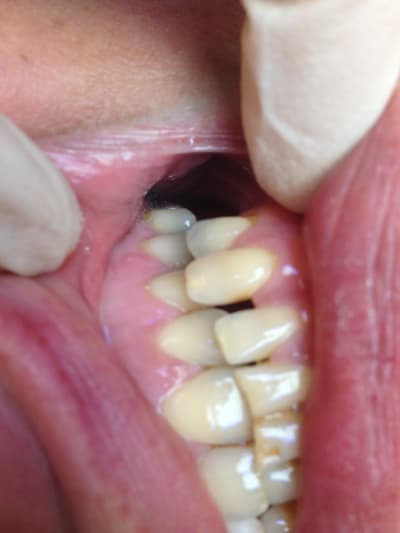

tu m'étonnes que la vis aies cassé 😊

Elle vient taper avec sa canine en plein sur sa latéral (2eme photo). Pas de dents En postérieur et articulé croisé.